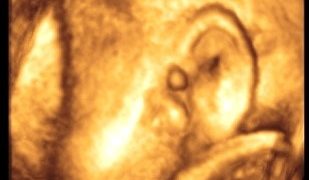

Caso del mese: Agosto 2018

Formulate la vostra Diagnosi. Le risposte vanno inviate via mail all’indirizzo sieogiovani@gmail.com Qui sotto puoi vedere la soluzione del caso del mese di Luglio 2018